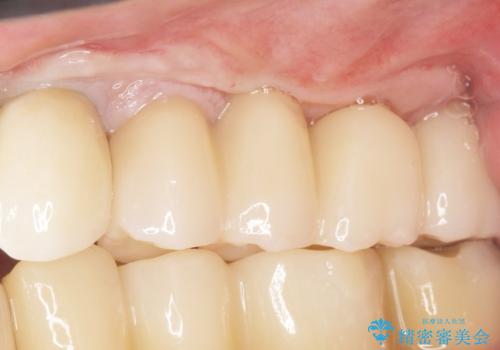

歯肉移植(FGG)による角化歯肉の獲得で長持ちするインプラントへ 50代男性

禁煙指導と歯周病治療後、左上臼歯部のソケットリフト(上顎洞底挙上術)及びインプラント治療(左上457埋入)を行いました。

インプラントが長持ちするように、角化歯肉(歯ブラシが当たっても痛くない固くしっかりした歯茎)の移植(遊離歯肉移植術:FGG)も行いました。

奥歯でしっかりと咬むことができるようになり、喜んで頂けました。

角化歯肉の移植により、ブラッシング時の歯ぐきの痛みもなくセルフコントロールも良好です。

インプラントの種類:スプラインツイスト(HAコーティング)

固定様式:スクリュー固定

クラウンの種類:ベレッツァクラウン